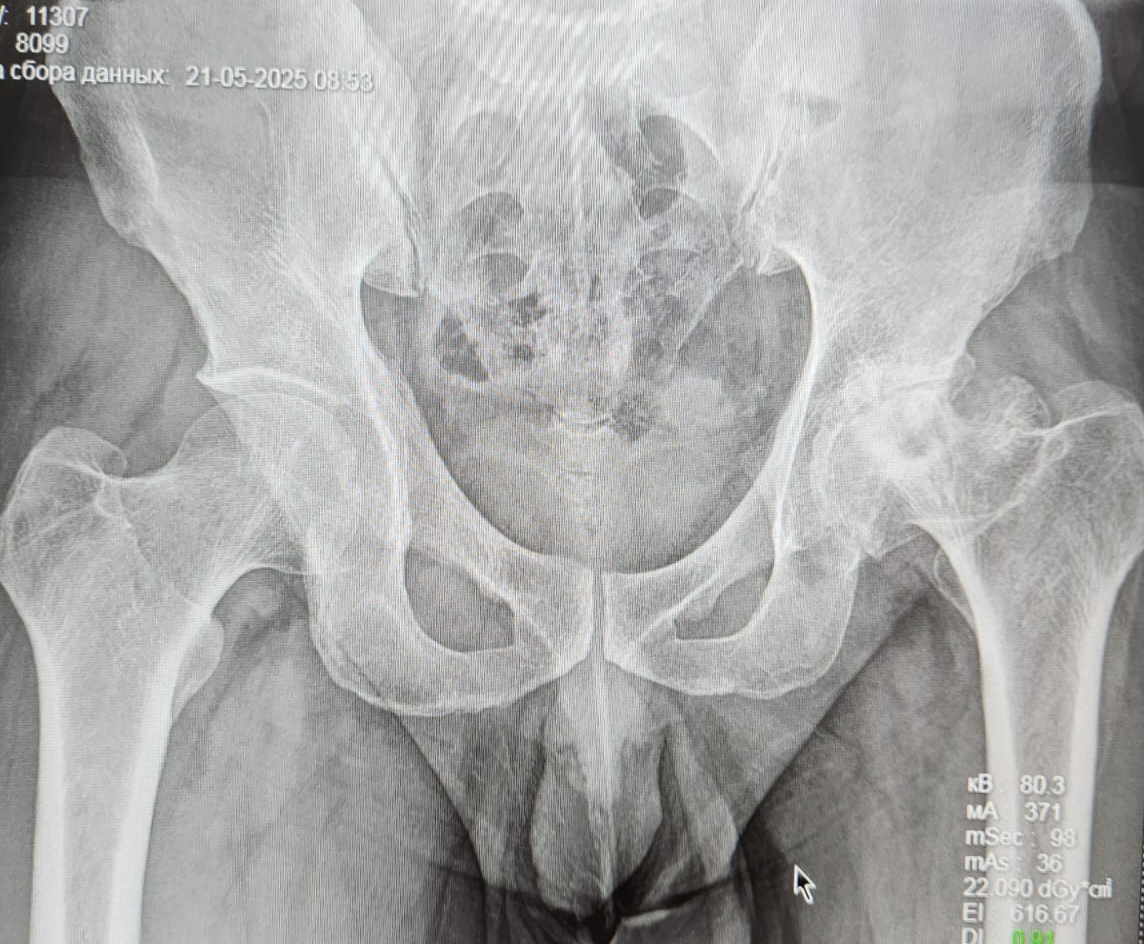

Критическая точка: боль стала постоянной, рентген показал почти полное исчезновение хряща (рис. 1).

Рисунок 1

Перенесенная в детстве болезнь Пертеса – асептический некроз головки бедренной кости, приведший к деформации головки